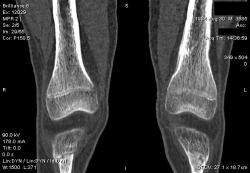

Мальчик 15 лет. Несколько месяцев назад начали беспокоить боли в коленных суставах. Травмы не было. Ребёнку был выставлен диагноз: болезнь Шлаттера, назначено лечение. На фоне лечения отмечалось значительное усиление болей, боли локализовались в левом коленном суставе. При дообследовании выявлена следующая рентгенологическая картина. Наши рентгенологи настаивают на срастающемся переломе. Но: 1) перелом без травмы? 2) бедро так не ломается

В голову приходит остеомиелит или опухоль.

Локальный гиперостоз, выраженный болевой синдром, структура губчатого вещества диафиза не изменена наводит только на остеойд-остеому.

Я бы на первое место поставила патологическую перестройку, так называемый, стрессовый перелом. Мальчик чем-нибудь занимается?

Согласна с Ola-la - рентгенологическая картина более всего соответствует стрессорному перелому, хотя для него характерна локализация в б/берцовой кости. Меня однако, смущает и настораживает клиника - это как раз тот случай, когда я бы не дала 100% гарантии, что так не может манифестировать остеосаркома... Поскольку другие методы (МРТ, сцинтиграфия) вряд ли помогут, я бы взяла пациента на короткое ( 2недели - месяц) динамическое наблюдение.

Да, на мой взгляд, состояние после обычного "травматического перелома" (трещина), не думаю, что имел место "патологический перелом", так как костная ткань "патологически изменена" минимально. "Перистальная реакция"локальная тоже есть, на КТ "локальная  зона склероза" - все это свидетельствует именно об этом. Хотя в памяти у меня хорошо отложился Ваш последний случай о локальном утолщении кортикального слоя, когда "яйца в гнезде" еще не было. То, что анамнестически "травмы не было" - ничего не значит. Вы, по всей видимости, тоже часто встречались с такими случаями, когда ребенок не акцентировал внимание на "травме", как таковой, хотя клиника есть, боль есть. Конечно, рентгенограммы - не дай бог - ни скиалогии, ни структуры.

Буквально заключение гистологов передать не могу (мой недочет, нужно было сразу выложить на сайтОй-ой-ой), но приблизительно помню - данных за специфический процесс нет, картина консолидирующегося перелома.

Так что, по всей видимости, это действительно был стресс-перелом. Который крайне редко встречается. Хоть статейку в журнал пишиУлыбаюсь.